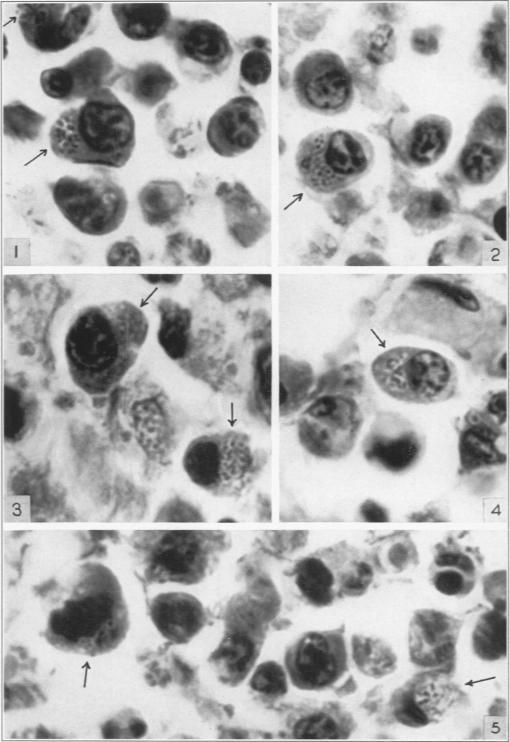

Intracellular bacilli in intestinal and mesenteric lesions of typhoid fever.

Am J Pathol. 1939 Sep;15(5):561-566.1.